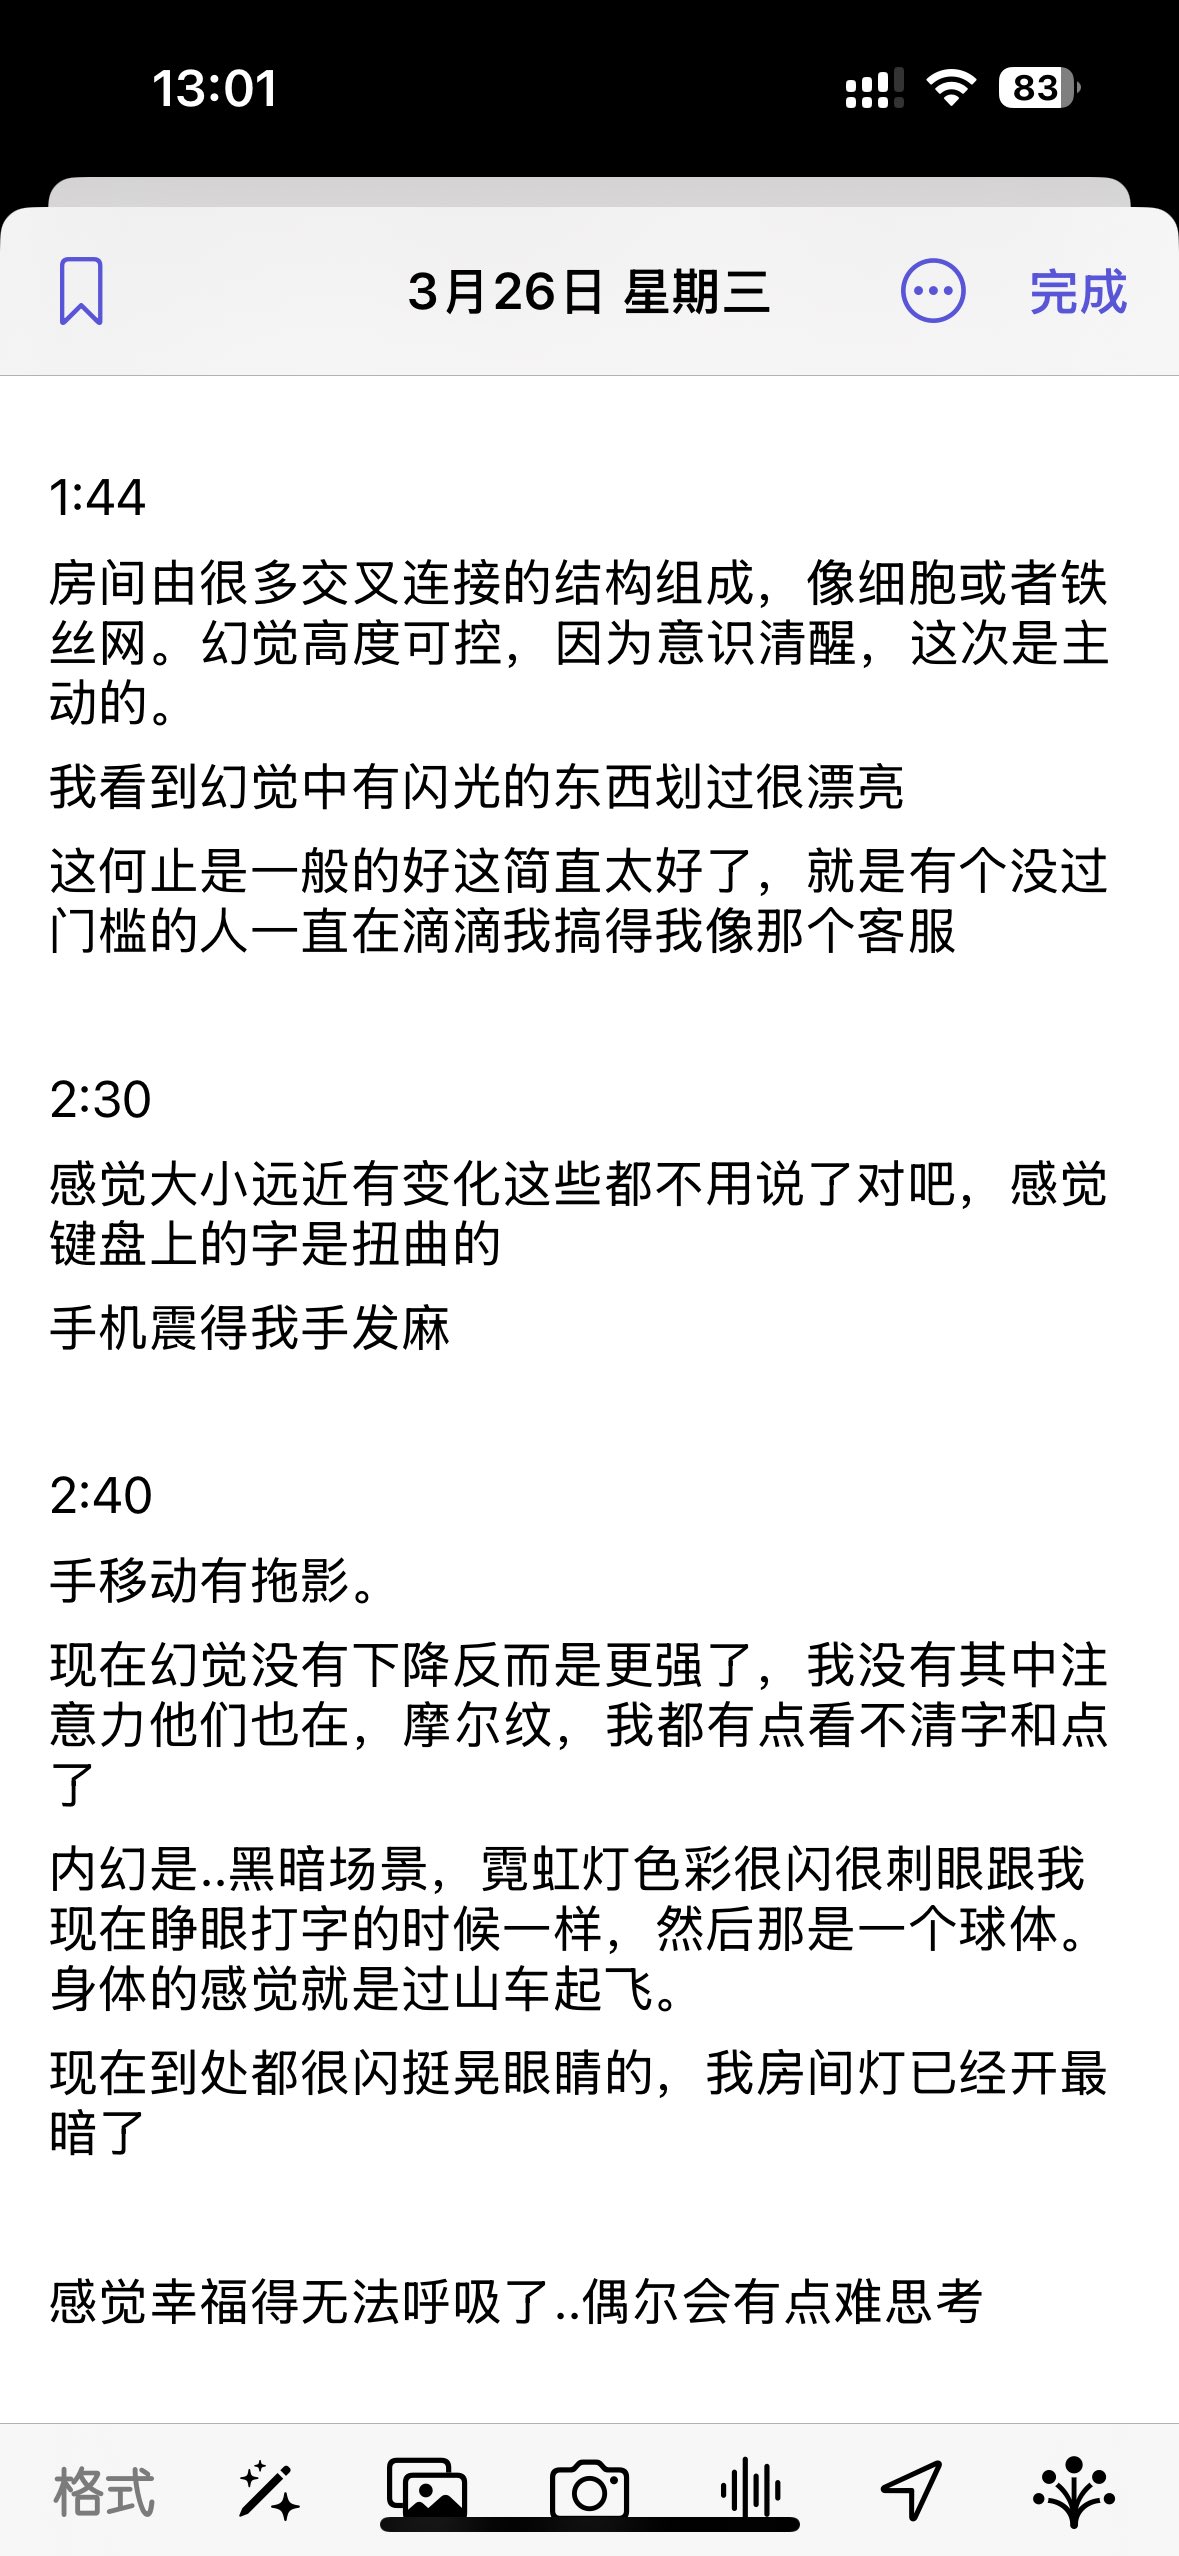

2024-08-14 11:34:53 UTC

甚至在第二天有余晖的感觉,虽然发生了很多破事但没怎么影响心情*抗焦虑&镇静

运动协调性稍差,表现为走路和站立时平衡不好

此剂量下对睡眠的改善作用,增加了慢波睡眠且没有影响rem,精力恢复+

FDA数据,在临床剂量下(75-600mg)普瑞巴林的依赖性低于bzd,并相比之下它产生的认知和精神运动障碍较轻 https://t.co/TJ7ZOQ7pbC